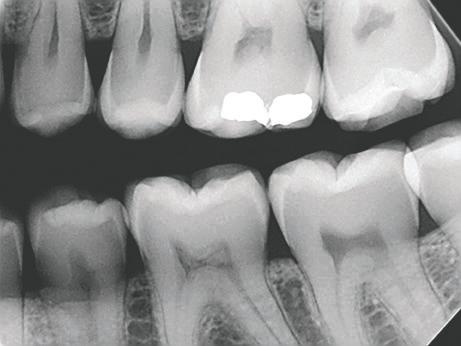

TrollBag for røntgensensorer

Supermyke trekk for sensorer og fosforplater. Helt uten lateks, lukt, smak og skarpe kanter. Lett å ta på og av, uten å ødelegge sensoren.

Tips: XL-trekket dekker både sensor og røntgenholder. En superenkel løsning som gjør hygienearbeidet mye enklere.

TrollBag for fosforplater

Supermyke poser for fosforplater.

Helt uten lateks, lukt, smak og skarpe kanter. Lett å ta på og av.

Leveres på rull i praktisk dispensereske.

Dekker sensor.

3,6*22cm.

500-pk. Før 1.048,#1

734,-

Vnr. 6509

#13190089

Dekker sensor. 4,0*22cm. 500-pk. Før 1.048,#13190090

Vnr. 6500

Fosforplate #1 49x29mm. 500-pk. Før 1.298,-

Fosforplate #2 50x36mm. 500-pk. Før 1.298,-

Vnr. 7783 974,-

Vnr. 7784

#13190401 #13190402